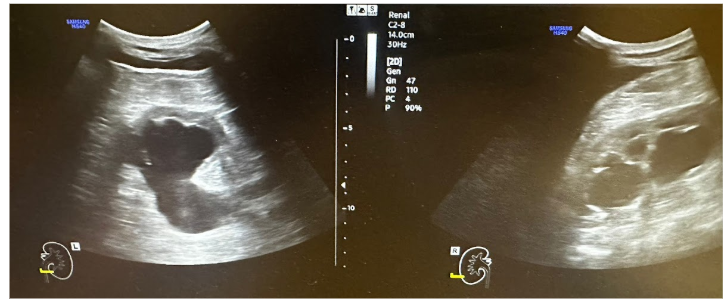

Tras la clínica presentada, se realiza una ecografía clínica abdominal con el fin de orientar el diagnóstico.

Hallazgos ecográficos

Ecografía clínica: Ureterohidronefrosis grado III bilateral con ectasia ureteral bilateral en toda su extensión. Probable proceso neoformativo urinario con dimensiones aproximadas de 5,61 x 2,74 cm.